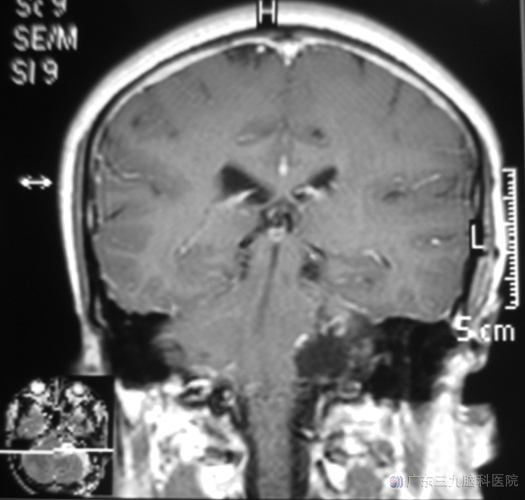

鲁明主任主刀,在全麻下行左侧桥小脑角区肿瘤切除术,显微镜下见灰白色肿瘤组织位于左侧桥小脑角,电生理监测下用超声刀分块切除肿瘤,部分肿瘤侵犯内听道,手术过程对面神经、三叉神经、舌咽神经、副神经、迷走神经及脑干等重要结构均保留完整。术后未出现后组颅神经损害的症状。病理结果为:神经鞘膜瘤。

▲手术后